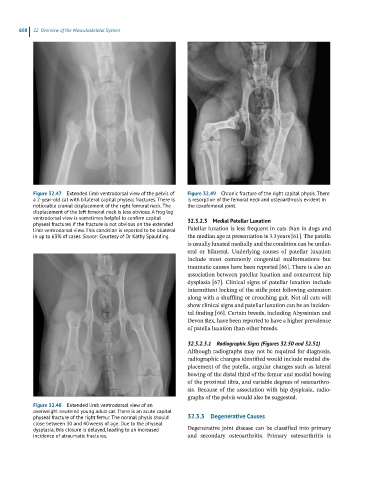

Figure 32.47 Extended limb ventrodorsal view of the pelvis of Figure 32.49 Chronic fracture of the right capital physis. There

a 2-year-old cat with bilateral capital physeal fractures. There is is resorption of the femoral neck and osteoarthrosis evident in

noticeable cranial displacement of the right femoral neck. The the coxofemoral joint.

displacement of the left femoral neck is less obvious. A frog leg

ventrodorsal view is sometimes helpful to confirm capital 32.3.2.3 Medial Patellar Luxation

physeal fractures if the fracture is not obvious on the extended

limb ventrodorsal view. This condition is reported to be bilateral Patellar luxation is less frequent in cats than in dogs and

in up to 63% of cases. Source: Courtesy of Dr Kathy Spaulding. the median age at presentation is 3.3 years [61]. The patella

Figure 32.48 Extended limb ventrodorsal view of an

overweight neutered young adult cat. There is an acute capital

physeal fracture of the right femur. The normal physis should 32.3.3 Degenerative Causes

close between 30 and 40 weeks of age. Due to the physeal

dysplasia, this closure is delayed, leading to an increased Degenerative joint disease can be classified into primary

incidence of atraumatic fractures. and secondary osteoarthritis. Primary osteoarthritis is